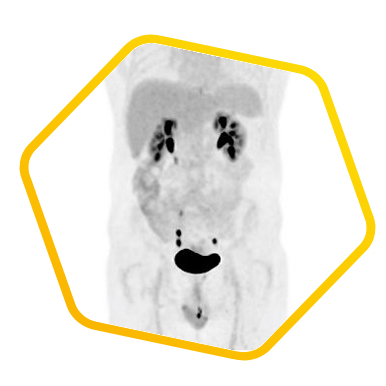

脑神经内分泌肿瘤

双示踪剂PET/CT (F-18 FDG及Ga-68 DOTATATE) 用於评估脑神经内分泌肿瘤体内的扩散情况

![]() [F-18] FDG |